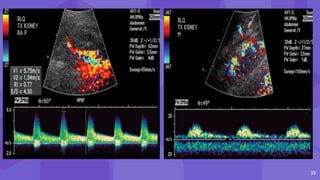

Post Biopsy Renal AVF and Pseudoaneurysm

● AVF Pseudoaneurysm

AVFs have a feeding

artery with a high-

velocity low-resistance

waveform at spectral

analysis

● narrow neck

● to-and-fro pattern of

blood flow

● yin-yang sign

14 Post Biopsy RenalAVF and Pseudoaneurysm ● AVF may form when an artery and vein are lacerated, whereas PA results when only the artery is lacerated ● AVF Pseudoaneurysm AVFs have a feeding artery with a high- velocity low-resistance waveform at spectral analysis ● narrow neck ● to-and-fro pattern of blood flow ● yin-yang sign